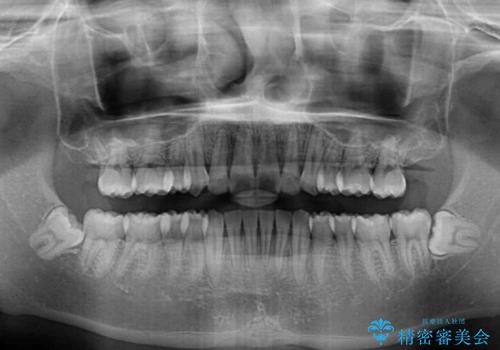

- 矯正治療の後戻りを気にして来院された患者様です。

後戻りは軽微であったので、インビザライン・ライトにより矯正治療を行うこととしました。

インビザライン・ライトは提供されるマウスピースの数に制限があり、通常のタイプよりもマウスピース提供期間が短くなっている一方、安価に治療を行うことができるプランです。

治療のゴールも変更できないため、軽微な歯列不正や、後戻り改善などに適しています。

矯正治療後は、再度後戻りすることを極力回避するために、下顎前歯の舌側を細いワイヤーを用いて保定することとしました。